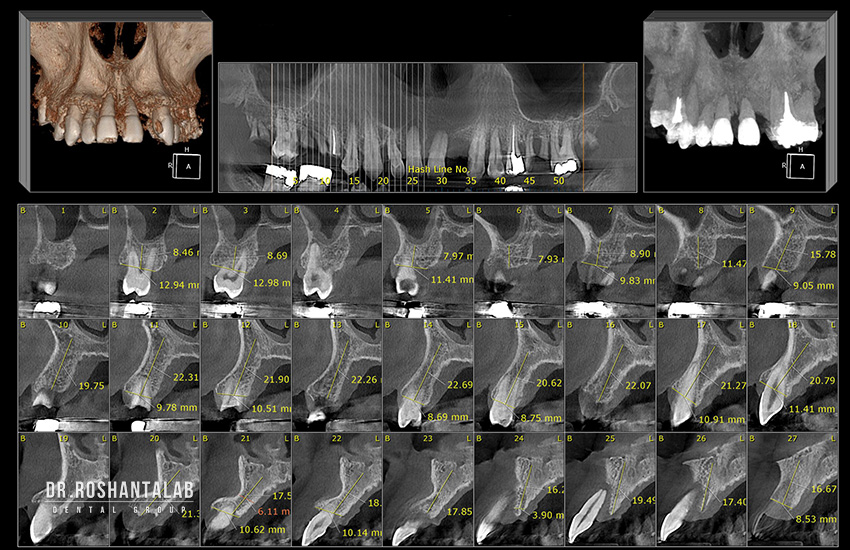

در ابتدای مراحل ایمپلنت دیجیتال، دندانپزشک یک ارزیابی کامل از وضعیت دهان بیمار انجام میدهد. این مرحله شامل معاینه فیزیکی، بررسی تاریخچه پزشکی و تصویربرداری است. کلیدیترین بخش، اسکن سهبعدی با دستگاه CBCT است که تصاویر دقیق از استخوان فک، موقعیت عصبها و سینوسها ارائه میدهد. این اسکن به دندانپزشک کمک میکند تا حجم و تراکم استخوان را اندازهگیری کند و اگر نیاز به پیوند استخوان باشد، آن را تشخیص دهد.

پس از اسکن، دادهها به نرمافزارهای دیجیتال منتقل میشوند. دندانپزشک با استفاده از این نرمافزارها، مدل سهبعدی دهان را ایجاد میکند و موقعیت ایدهآل ایمپلنت را شبیهسازی میکند. این مرحله معمولاً ۳۰ تا ۶۰ دقیقه طول میکشد و بدون درد است. اگر بیمار شرایط خاصی مانند کمبود استخوان داشته باشد، ممکن است پیوند استخوان در این مرحله برنامهریزی شود.